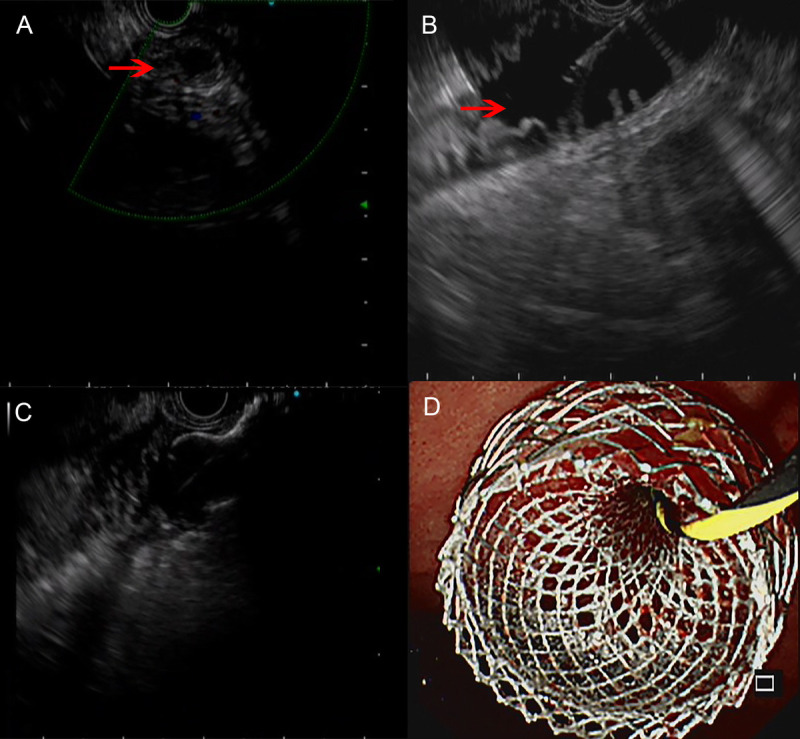

EUS-led breakthrough: An innovative journey to overcome complete gastric outlet obstruction by gastroenterostomy (with video).